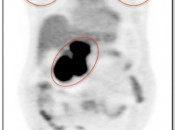

CT Portion of the Exam:  Its value lies in its excellent anatomic detail, as demonstrated in the case above.  In this patient presenting for post-treatment assessment of lymphoma, the CT clearly demonstrates abnormal soft tissue density above and below the diaphragm.  From the CT scan, we know abnormal soft tissue exists, its size and precisely where it is located. What we do not know from the CT scan is the answer to the ultimate clinical question: Does this remaining soft tissue represent active malignancy or post-therapeutic scarring — Does this patient still have cancer? For the answer, we must turn to the PET portion of the examination.

PET Portion of the Exam: Although of extremely limited anatomic value, the PET study has the impressive ability to determine whether the residual soft tissue on the CT scan represents active malignancy or post-therapeutic scar tissue. In this case, the intense metabolic activity is consistent with active lymphoma both above and below the diaphragm.

Images are then reconstructed to permit viewing in the axial, sagittal and coronal planes.

Three sets of images are produced for interpretation by the radiologist (addressed in greater in detail, here).

1. CT images (in three planes)

2. Non-Attenuation Corrected PET Images

3. Attenuation Corrected PET Images [Fig. 3]